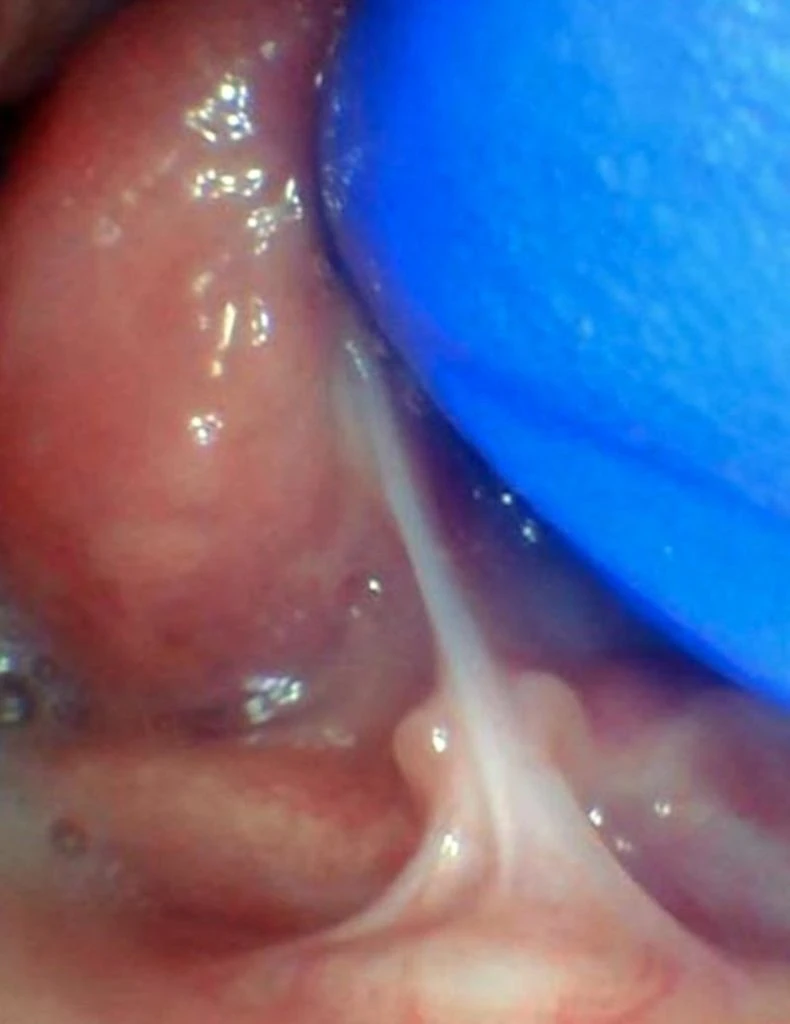

These images show the spectrum of lip restriction in a child.

View lip restrictions

These images show the spectrum of tongue restriction in a child.

View tongue restrictions

These images show the spectrum of posterior tongue restriction in a child.

View posterior tongue restrictions